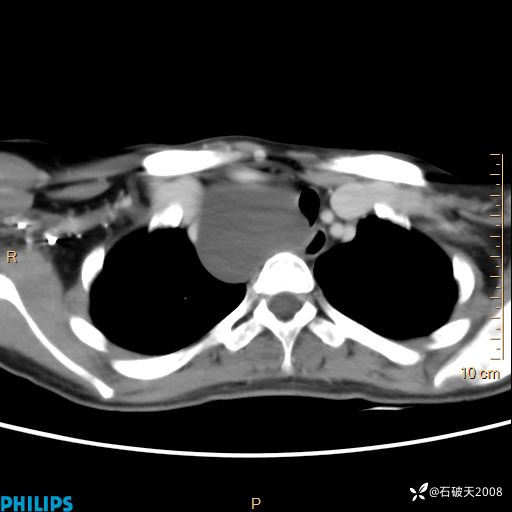

影像诊断要密切结合临床,真的很有必要(病理已公布)

女 21岁 主 诉:发现右侧颈部肿物18年余。

现病史:18年余前患者无明显诱因发现颈部偏右侧有一肿物,具体大小不明确,咳嗽、憋气时肿物增大,局部无疼痛,无吞咽不适,无胸闷及呼吸困难,至当地医院检查考虑良性病变(具体不详)并未做特殊处理,现患者自觉肿物随年龄增长而进一步变大,今日至我院行颈部CT平扫+增强提示:1.右侧颈根部、锁骨上窝及纵隔内异常密度影,考虑良性病变,淋巴管瘤?囊肿?请结合临床。2.双侧颈部小淋巴结。建议结合临床及其他相关检查。现为行进一步治疗,门诊以“颈部局部肿物”为诊断收住我科,发病来患者神志清,精神可,饮食睡眠可,大小便正常,体重无下降。

冠状位